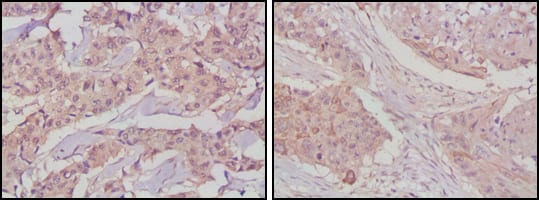

| IHC | 1/200 - 1/1000 | Human,Mouse,Rat |

GSK3B-specific antibodies are widely used in techniques like Western blotting, immunohistochemistry (IHC), immunofluorescence (IF), and immunoprecipitation (IP). Many commercial antibodies target distinct epitopes, including phospho-specific variants that detect activated or inactivated forms. Researchers often select monoclonal or polyclonal antibodies based on experimental needs, considering factors like species reactivity (human, mouse, rat), specificity validated by knockout/knockdown controls, and compatibility with assay conditions. Antibodies from suppliers like Cell Signaling Technology, Abcam, and Santa Cruz Biotechnology are commonly cited, with validation data crucial for ensuring reproducibility. Given GSK3B's multifaceted roles, high-quality antibodies remain vital for elucidating its complex regulatory networks and therapeutic targeting in disease models.